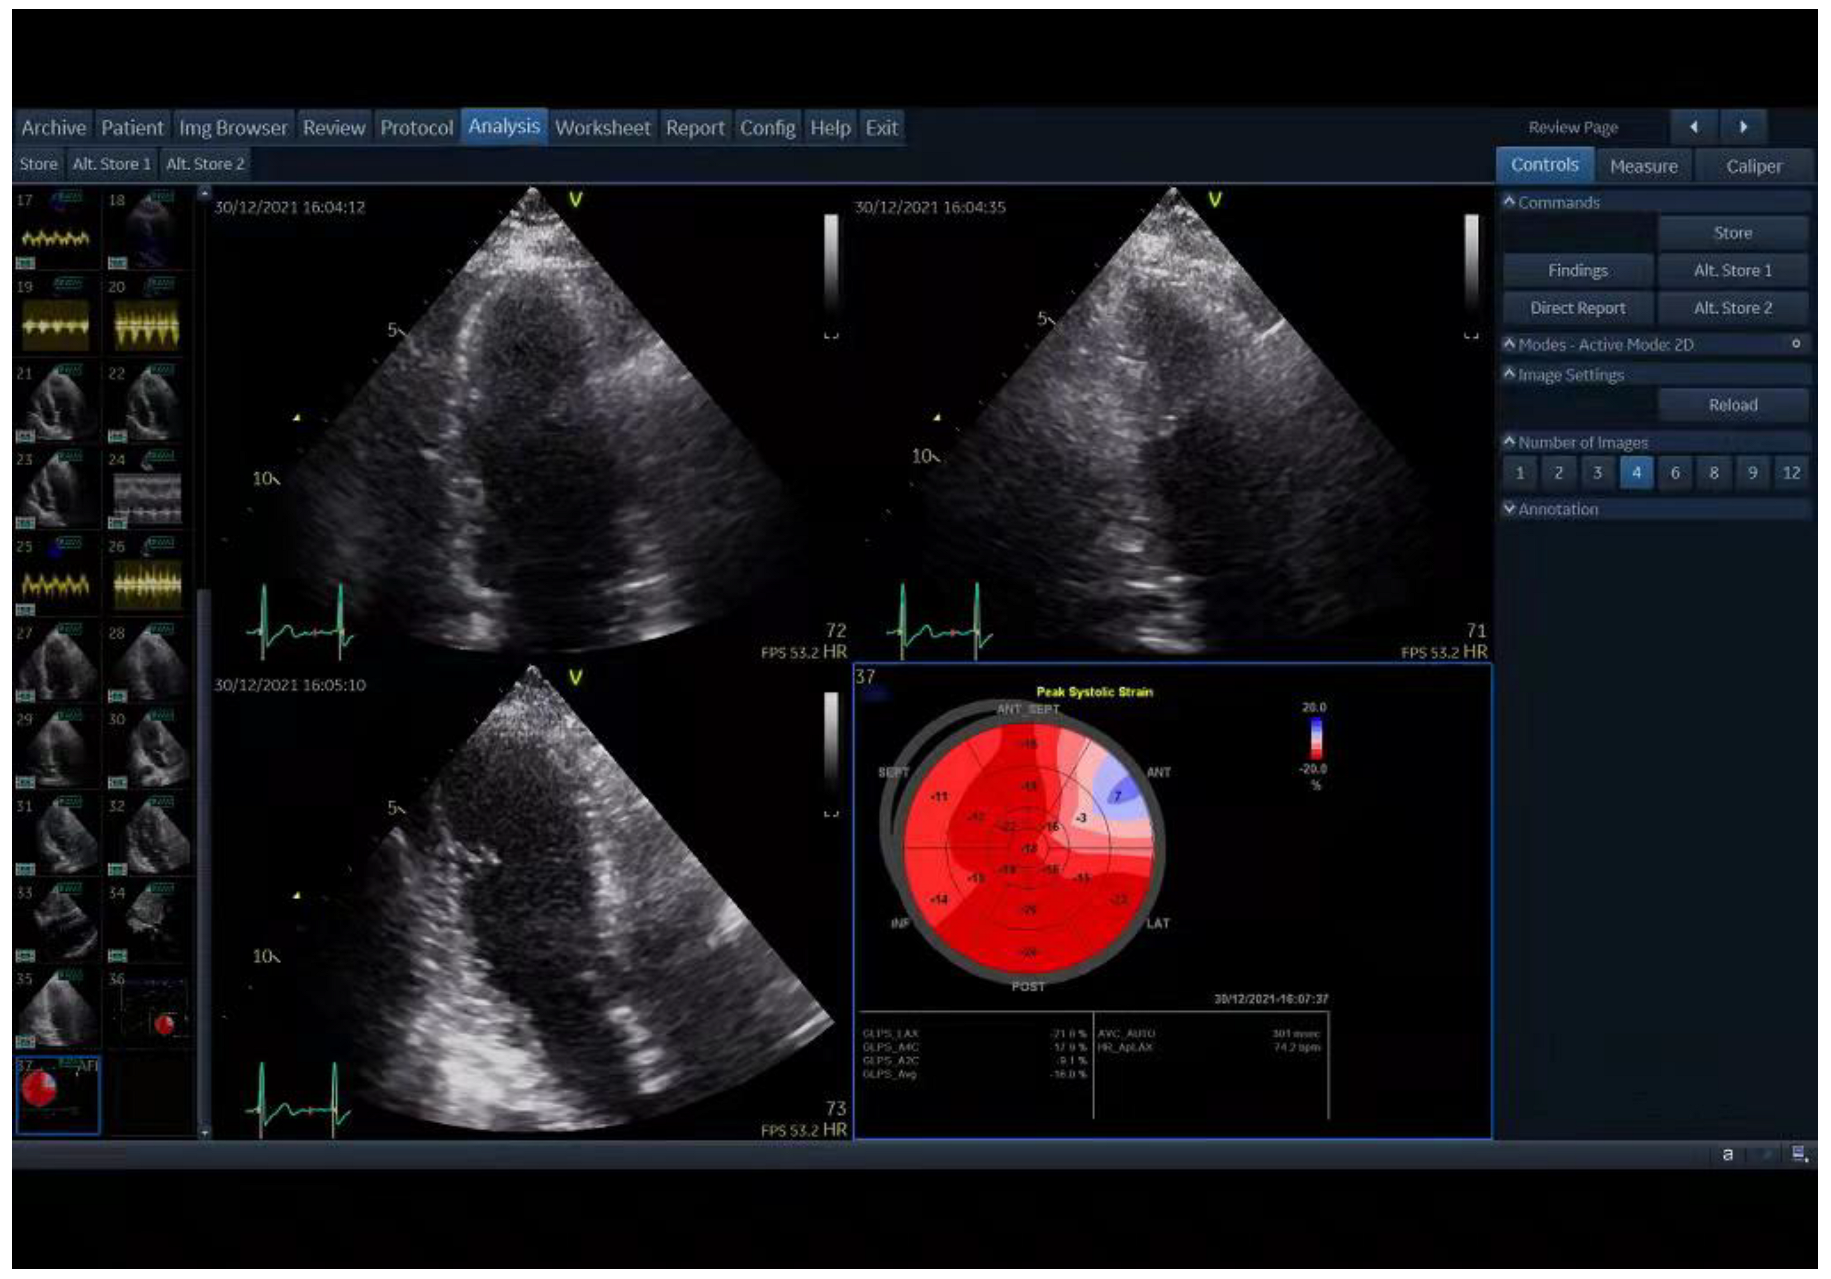

2.4. Two-Dimensional Speckle-Tracking Echocardiography (2D-STE)